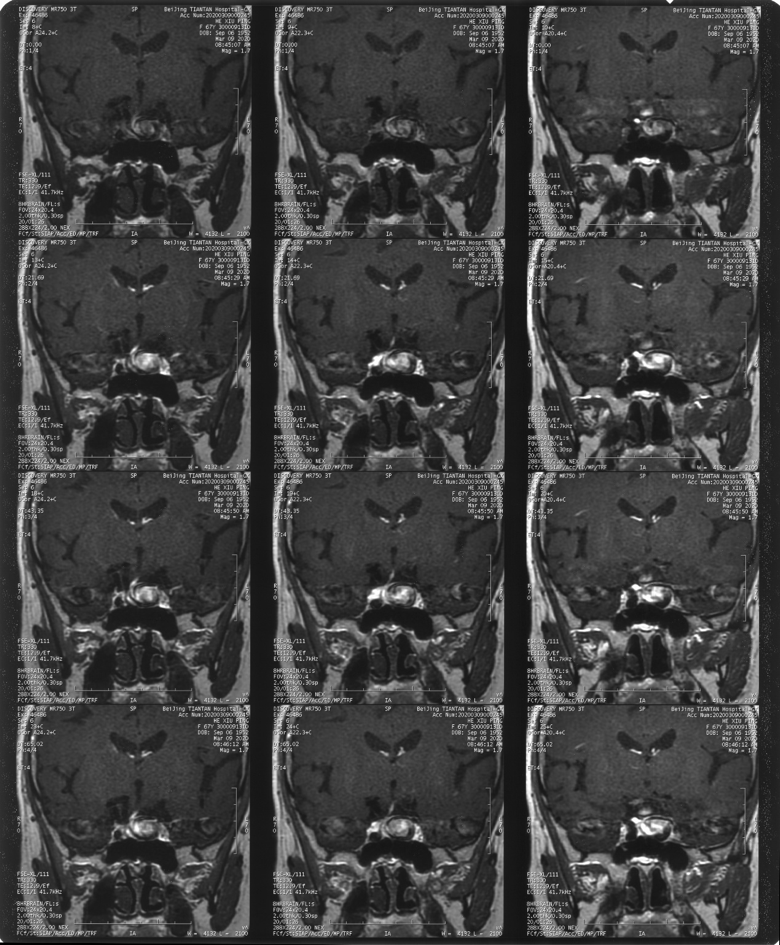

造影见左侧颈内动脉海绵窦段巨大动脉瘤,瘤体远端海绵窦水平段血管狭窄,眼动脉段血管扩张,左侧A1段缺如

本例患者动脉瘤位于海绵窦段,眼动脉段血管同时存在一定扩张异常,患者无明显高血压病史,从出血角度而言该患者相对出血风险并非极高。但根据核磁情况,尽管该动脉瘤位于海绵窦段,但已经有一部分瘤体突入颅内,一旦发生破裂出血,有一定可能进入蛛网膜下腔。且患者近期出现头晕及单眼黑朦,考虑与血流瘀滞于动脉瘤内有关。核磁上同样也可以看到瘤壁大量的血栓沉积,未来发生脑梗死的风险较大。此外,家属与患者对疾病的恐惧与治疗的决心也是我们最终决定施行手术治疗的原因之一。